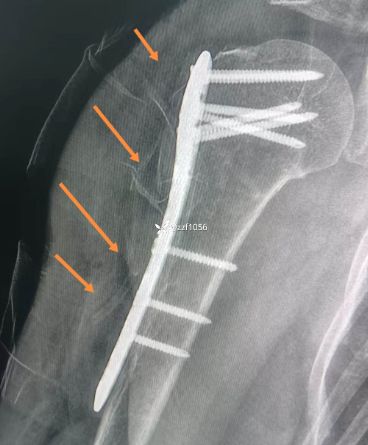

周末休息,下午管床医生给我打电话急匆匆说:「主任,17 床 80 岁老太太那位患者给她换药拔引流管时拔断了,我都没怎么使劲。一部分残留到了伤口里面了,怎么办?我带患者拍了个片发给你。」

从这个部位断了,应该是挂针挂住了

记得当时给缝合的兄弟特意交代:肌肉不要缝,只缝深筋膜和皮下就好了,结果还变成这样;医生真是如履薄冰,只能谨慎谨慎再谨慎。